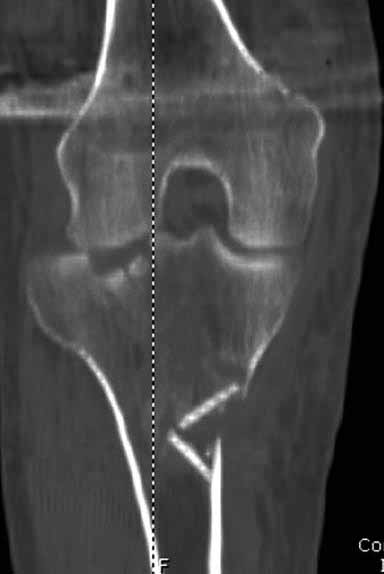

Здравствуйте уважаемые коллеги!Сегодня обратился больной 35л. Травму получил 3 мес.назад, упал в яму, лечился в отдаленном районе гипсовой повязкой, 1 месяц назад гипс сняли , и больной начал ходить с нагрузкой, постепенно появилась деформация коленного сустава, неустойчивость и боли. Локально: деформация коленного сустава, голень смещена кзади- типа подвывиха, разгибание 170гр. Сгибание 150гр.симптомов повреждение коллатеральных и крестообразных связок определить не удается из-за боли и контрактуры. Первичных снимков пока нет, обещали принести, имеется снимки через 2 месяца после травмы без гипса, недельной давности снимки в прямой проекции и К Т. Похоже, что импрессия переднемедиальной части внутреннего мыщелка б/берцовой кости, отрыв межмыщелкового возвышения.

На снимке типичный перелом медиального тибиал плато с передним смещением (подвывих) по Schatzker IV. Консервативное лечение без медиальной опоры не может удержать деформирующие силы, и из-за вторичного смещения мыщелка конечность смещается в варус. Кроме передних смещений еще встречаются сложные фронтальные варианты переломов, и тогда голень подвывихивается кпереди.

А в данном случае мыщелок сросся со смещением кпереди и ротирован. За счет интактной наружной колонны опороспособность конечности сохранена, но остается варус и экстензия конечности. Для предоперационного расчета необходимо сделать на всю длину конечности рентгенограмму, а в остром периоде КТ и 3-мерный снимок помогут лучше ориентироваться в характере перелома.

Остеотомия с разворотом медиального мыщелка, и для фиксации можно применить параллельные субхондральные межмыщелковые шурупы. Дополнительная медиальная Smith-Nephew PERI-LOC™ (Periarticular Locked Plating System) пластина. При отсутствии специальной пластины можно адаптировать Tomofix для высокой остеотомии. Доступ прямой медиальный через pes anserinus или через интервал pes с medial gastrocnemeus.